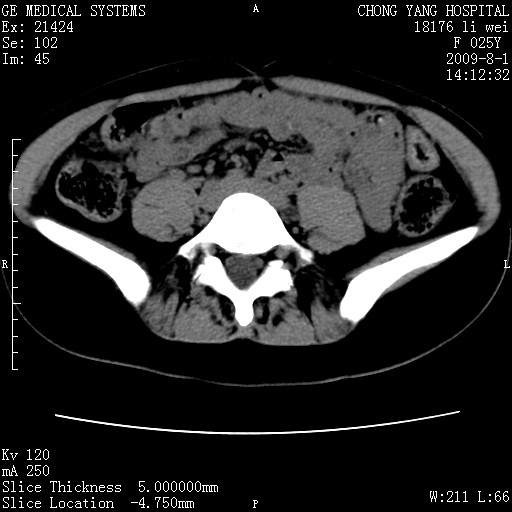

以下是引用pujunzhi在2009-8-1 20:23:00的发言:[br]胸椎旁及背部肌间良性病变,范围广,边界清,沿肌间生长,考虑淋巴管瘤、血管瘤,建议增强扫描。

以下是引用拾荒者在2009-12-30 21:45:00的发言:[br]ct21383:神经纤维瘤病( nf) [br] [br] 神经纤维瘤病。四肢都有,影响美观,四肢上的手术了。[br] [br] [br]谢谢!